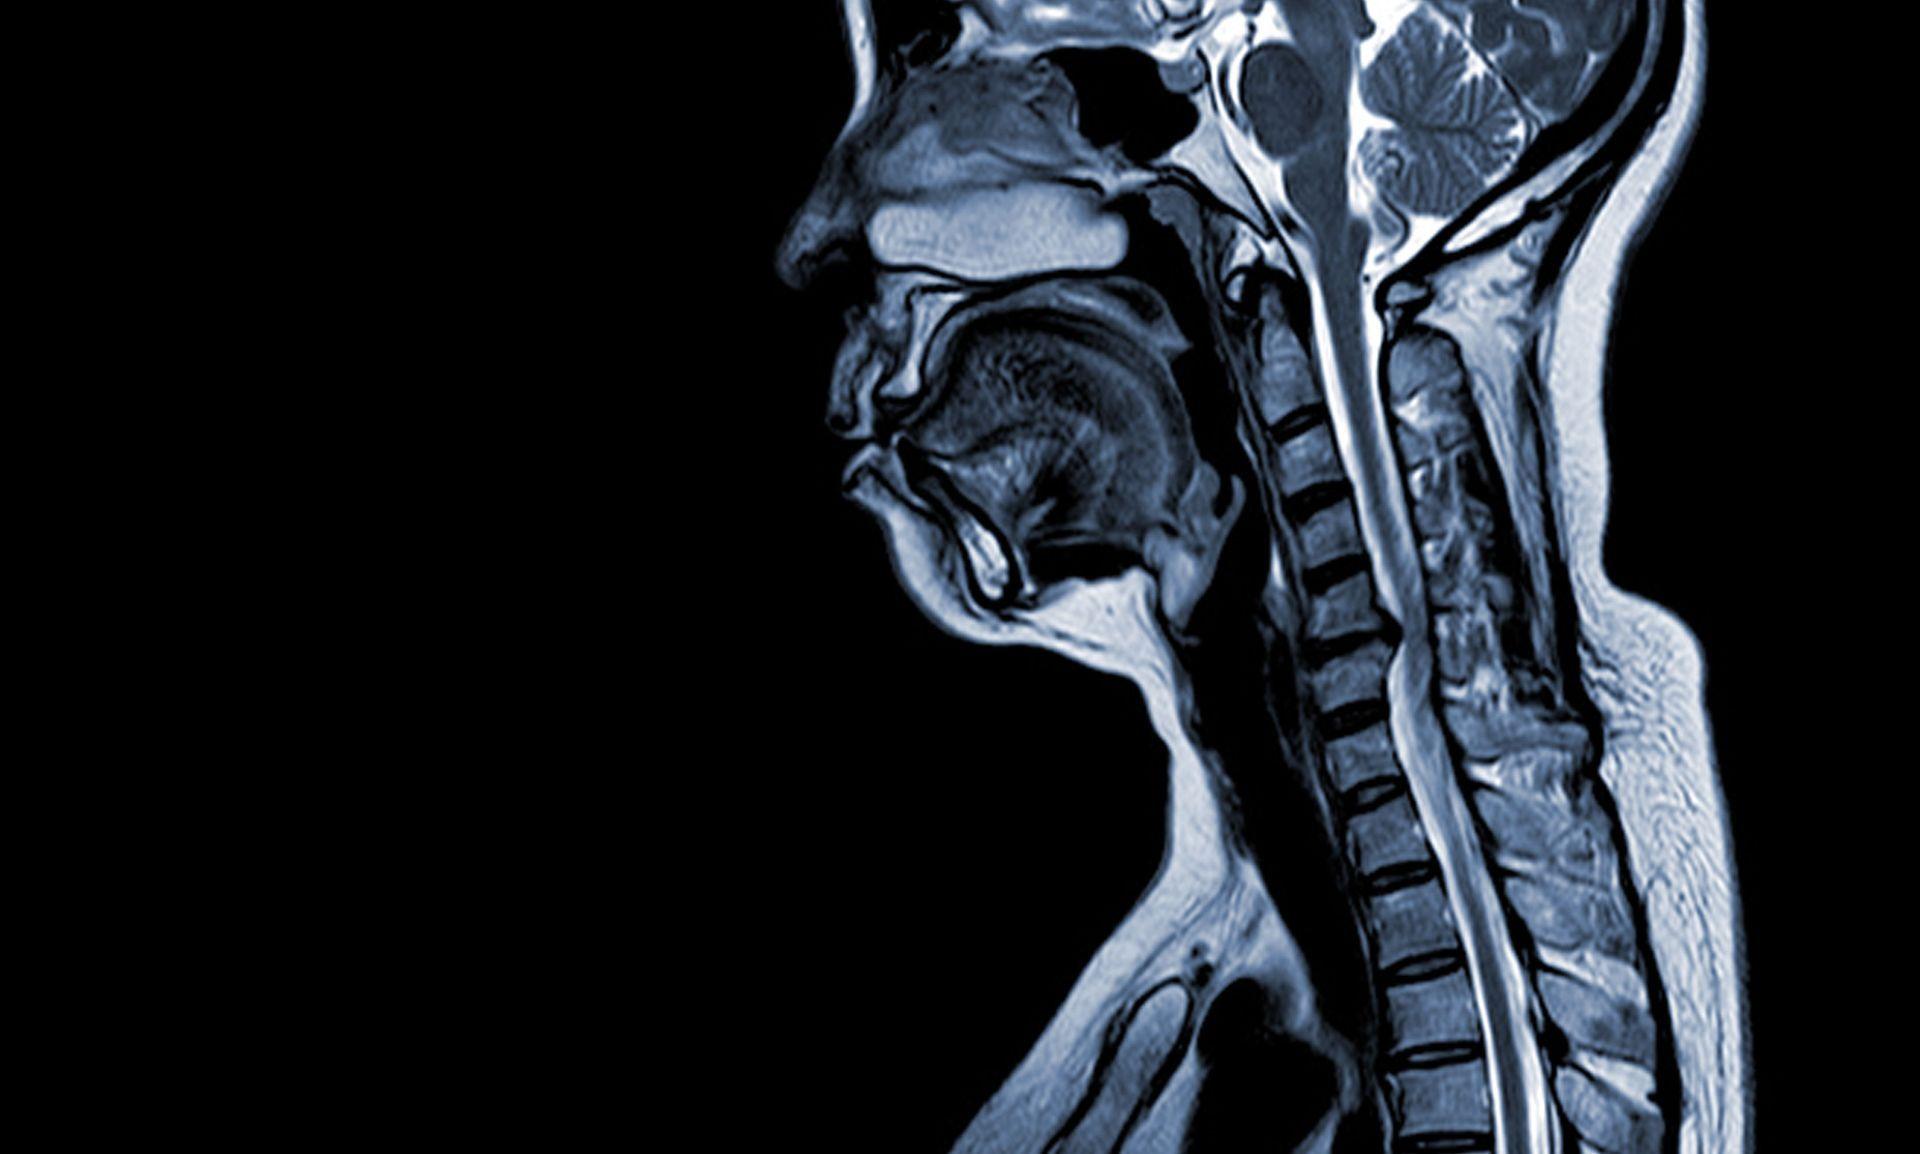

C5-C6 Disc Herniation